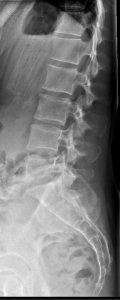

Radiographie du Rachis lombaire

Pour une radiographie du rachis lombaire, aucune préparation n'est requise. Il est recommandé d'enlever tous les bijoux avant de se présenter.

Vous serez allongés sur le dos avec les bras placés derrière la tête.

La durée de l'examen est d'environ 5 minutes. Un ou plusieurs clichés radiographiques seront effectués. Le manipulateur vous positionnera en fonction de l'incidence radiologique à réaliser. Sauf indication contraire, il sera important de ne pas bouger durant la prise de clichés.

Après la fin de la radiographie du rachis lombaire, vous pourrez continuer vos activités de la journée sans problème. S'il y a eu une injection, le manipulateur en radiologie retirera le cathéter et il vous sera recommandé de boire beaucoup d'eau afin d'éliminer au mieux le produit de contraste.

Avant de passer une radiographie du rachis lombaire, il est primordial de signaler si vous êtes ou pensez être enceinte. En effet, vous devrez passer l'examen sous certaines conditions.